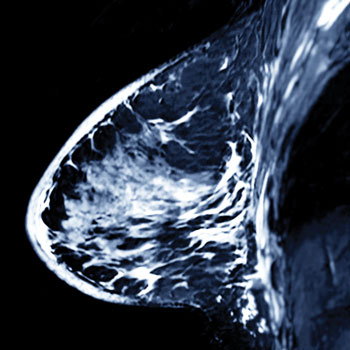

A pathogenic sequence variation in either the BRCA1 or BRCA2 gene occurs in about one in 400 people, according to the National Cancer Institute. These mutations are associated with a 70% lifetime risk of breast cancer and a 20% to 40% lifetime risk of ovarian cancer. Recent studies in JAMA Oncology showed that magnetic resonance imaging (MRI) can significantly reduce breast cancer mortality in women with a BRCA1 mutation and preventive oophorectomy can significantly reduce all-cause mortality in women with either mutation. But these options can only be considered if a mutation is known.

Prophylactic mastectomy, oophorectomy, and salpingectomy are potential options for decreasing cancer risk in patients with a BRCA mutation. If a patient is not ready to take these steps, however, routine breast screening with MRI could also be an option. Most guidelines recommend annual MRIs for women with BRCA mutations, and while mammography can also be used in those groups, it is not advised in younger women with BRCA mutations, who tend to have denser breast tissue, according to Dr. Olopade.